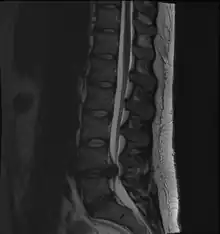

- Magnetic resonance imaging is the gold standard study for confirming a suspected LDH. With a diagnostic accuracy of 97%, it is the most sensitive study to visualize a herniated disc due to its significant ability in soft tissue visualization. MRI also has higher inter-observer reliability than other imaging modalities. It suggests disc herniation when it shows an increased T2-weighted signal at the posterior 10% of the disc. Degenerative disc diseases have shown a correlation with Modic type 1 changes. When evaluating for postoperative lumbar radiculopathies, the recommendation is that the MRI is performed with contrast unless otherwise contraindicated. MRI is more effective than CT in distinguishing inflammatory, malignant, or inflammatory etiologies of LDH. It is indicated relatively early in the course of evaluation (<8 weeks) when the patient presents with relative indications like significant pain, neurological motor deficits, and cauda equina syndrome. Diffusion tensor imaging is a type of MRI sequence used for detecting microstructural changes in the nerve root. It may be beneficial in understanding the changes that occur after herniated lumbar disc compresses a nerve root, and might help in differentiating the patients that need surgical intervention. In patients with a high suspicion of radiculopathy due to lumbar disc herniation, yet the MRI is equivocal or negative, nerve conduction studies are indicated.[46] T2-weighted images allow for clear visualization of protruded disc material in the spinal canal.

MRI scan of cervical disc herniation between C5 and C6 vertebrae

MRI scan of cervical disc herniation between C6 and C7 vertebrae